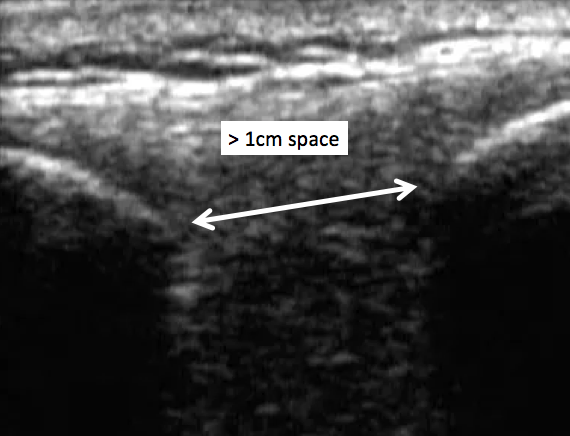

- Then rotate into the long axis view (as seen in the image below), and mark spaces between the spinous

While in the long axis view, assess the distance between the spinous processes, and compare width between L3-L4 and L4-L5. A nice big target is considered > 1cm